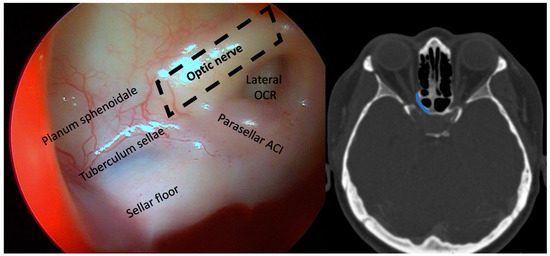

2.3. Surgical Technique